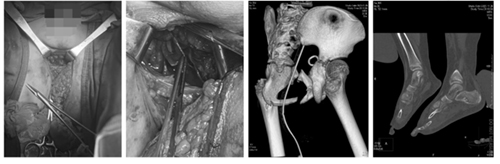

麻醉后,手术团队探查见患儿自阴囊根部至尾骨处有一巨大不规则裂口,组织碎烂外翻,创腔向后直至尾骨后方,左侧臀部、股部、左大腿内侧及腰部皮肤脱套游离,形成巨大空腔。直肠仅右侧有少量皮肤与肛门相连,前后和左侧碎烂游离回缩。尿道完全断裂,近端剥离回缩,可见耻骨断端。术中诊断为会阴裂伤累及肛门括约肌,尿道完全断裂,会阴、臀部及左大腿内侧及腰部皮肤广泛撕脱伤,骨盆多发骨折,左足多发骨折,肺挫伤。

患儿肛门部严重外伤,直肠仅右侧有少量皮肤与肛门相连,前后和左侧直肠游离回缩;肛门周围组织碎烂外翻,并形成巨大空腔。为保证患儿术后进食及排便,便于会阴和股部臀部的创面愈合,手术团队进行了乙状结肠造瘘术,利用右侧少量残存组织行肛门成形术,避免了会阴部受损组织的感染及延迟愈合。

因患儿会阴部严重外伤,伴有骨盆多发骨折,患儿尿道完全断裂,断端回缩。为尽快恢复尿道连续性,手术团队对于尿道断裂,首先进行了超声引导下耻骨上膀胱造口及导尿管置入术,于会阴部仔细探查后,将完全断裂的尿道进行了Ⅰ期经会阴尿道修复,避免了对会阴或耻骨联合上组织的二次损伤。鉴于儿童骨盆及会阴部的严重外伤,与小儿骨外科专家充分研判后,骨盆多发骨折给予了外固定支具固定;左足多发骨折给予了石膏固定。